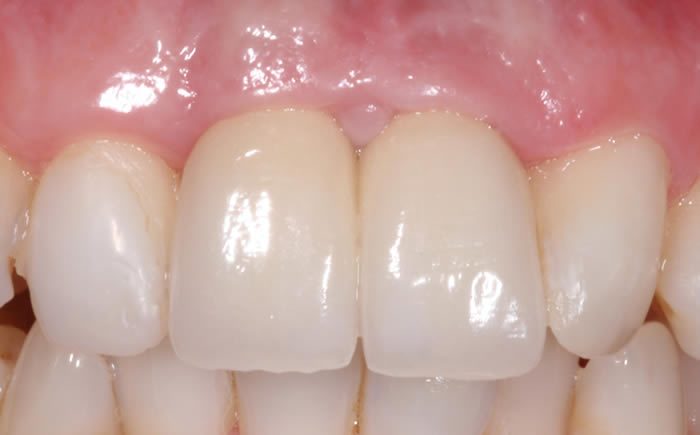

Before & After Gallery

More front teeth replaced by dental implants

Case Three (4 images)